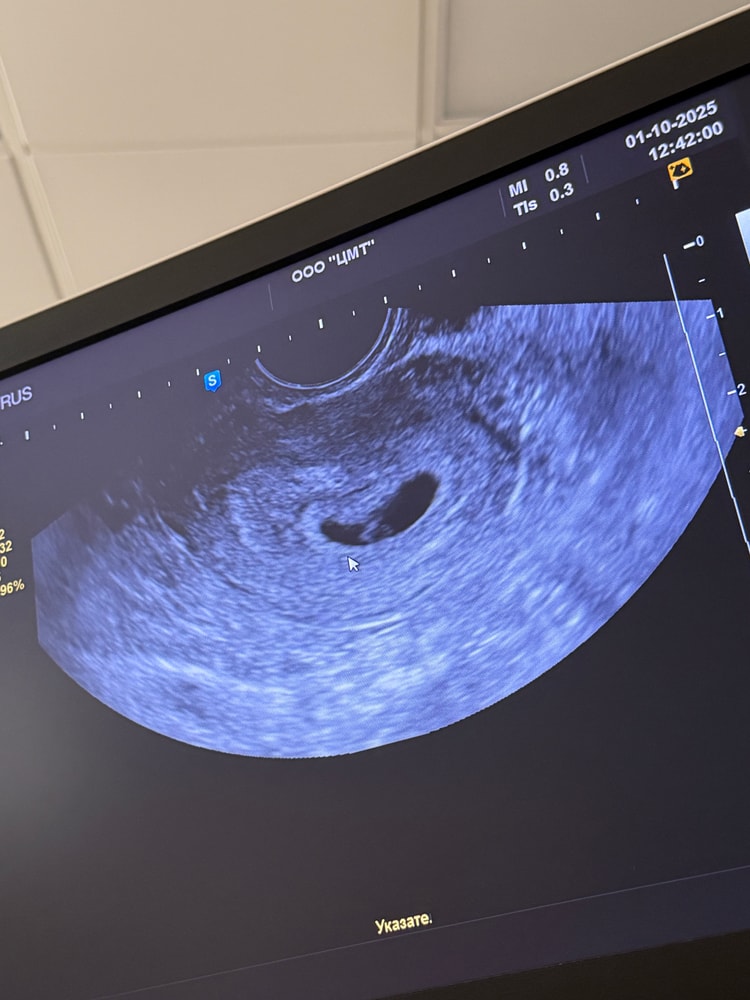

Нашли на узи маленькое колечко. Ктр- 2,6 жм- 2,0. Сердечко слушать недели через 1,5-2. Но вот какие у меня странные симптомы: ощущение как будто знобит при болезни, хочется надеть на себя 10 слоев одежды, ломит тело при этом температура тела обычная. Сильно болит голова и горло. У кого какие были симптомы на сроке 5-6 недель?

Анастасия, мне сегодня сделали узи. Эмбрион 4.1 и есть сердцебиение. Правда мне его не включили послушать, но я видела движение сердечка😭🤍